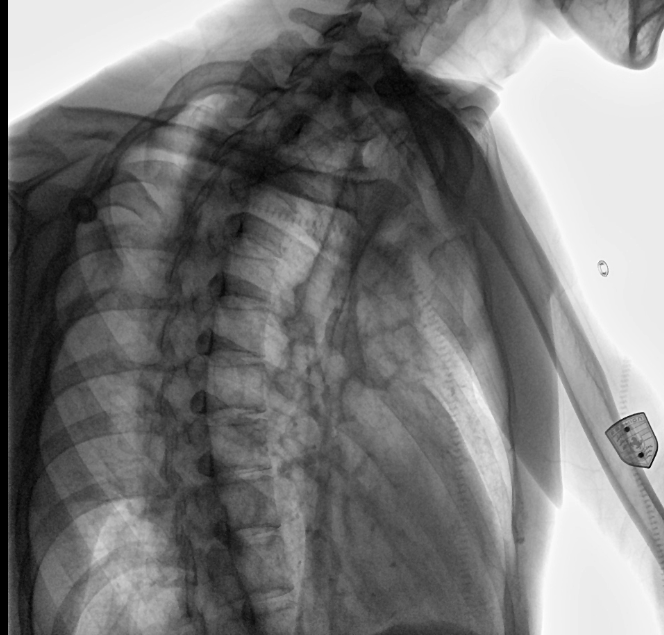

位于衡水市中醫(yī)醫(yī)院的動(dòng)態(tài)平板數(shù)字化X射線系統(tǒng)DTP571具備高速高清點(diǎn)片功能。這是一款對(duì)放射科十分友好的產(chǎn)品。因?yàn)樗迅咚俸透咔妩c(diǎn)片結(jié)合,既能方便影像技師有效地抓拍需要的病灶的影像,又能給予影像醫(yī)生清晰的影像進(jìn)行診斷